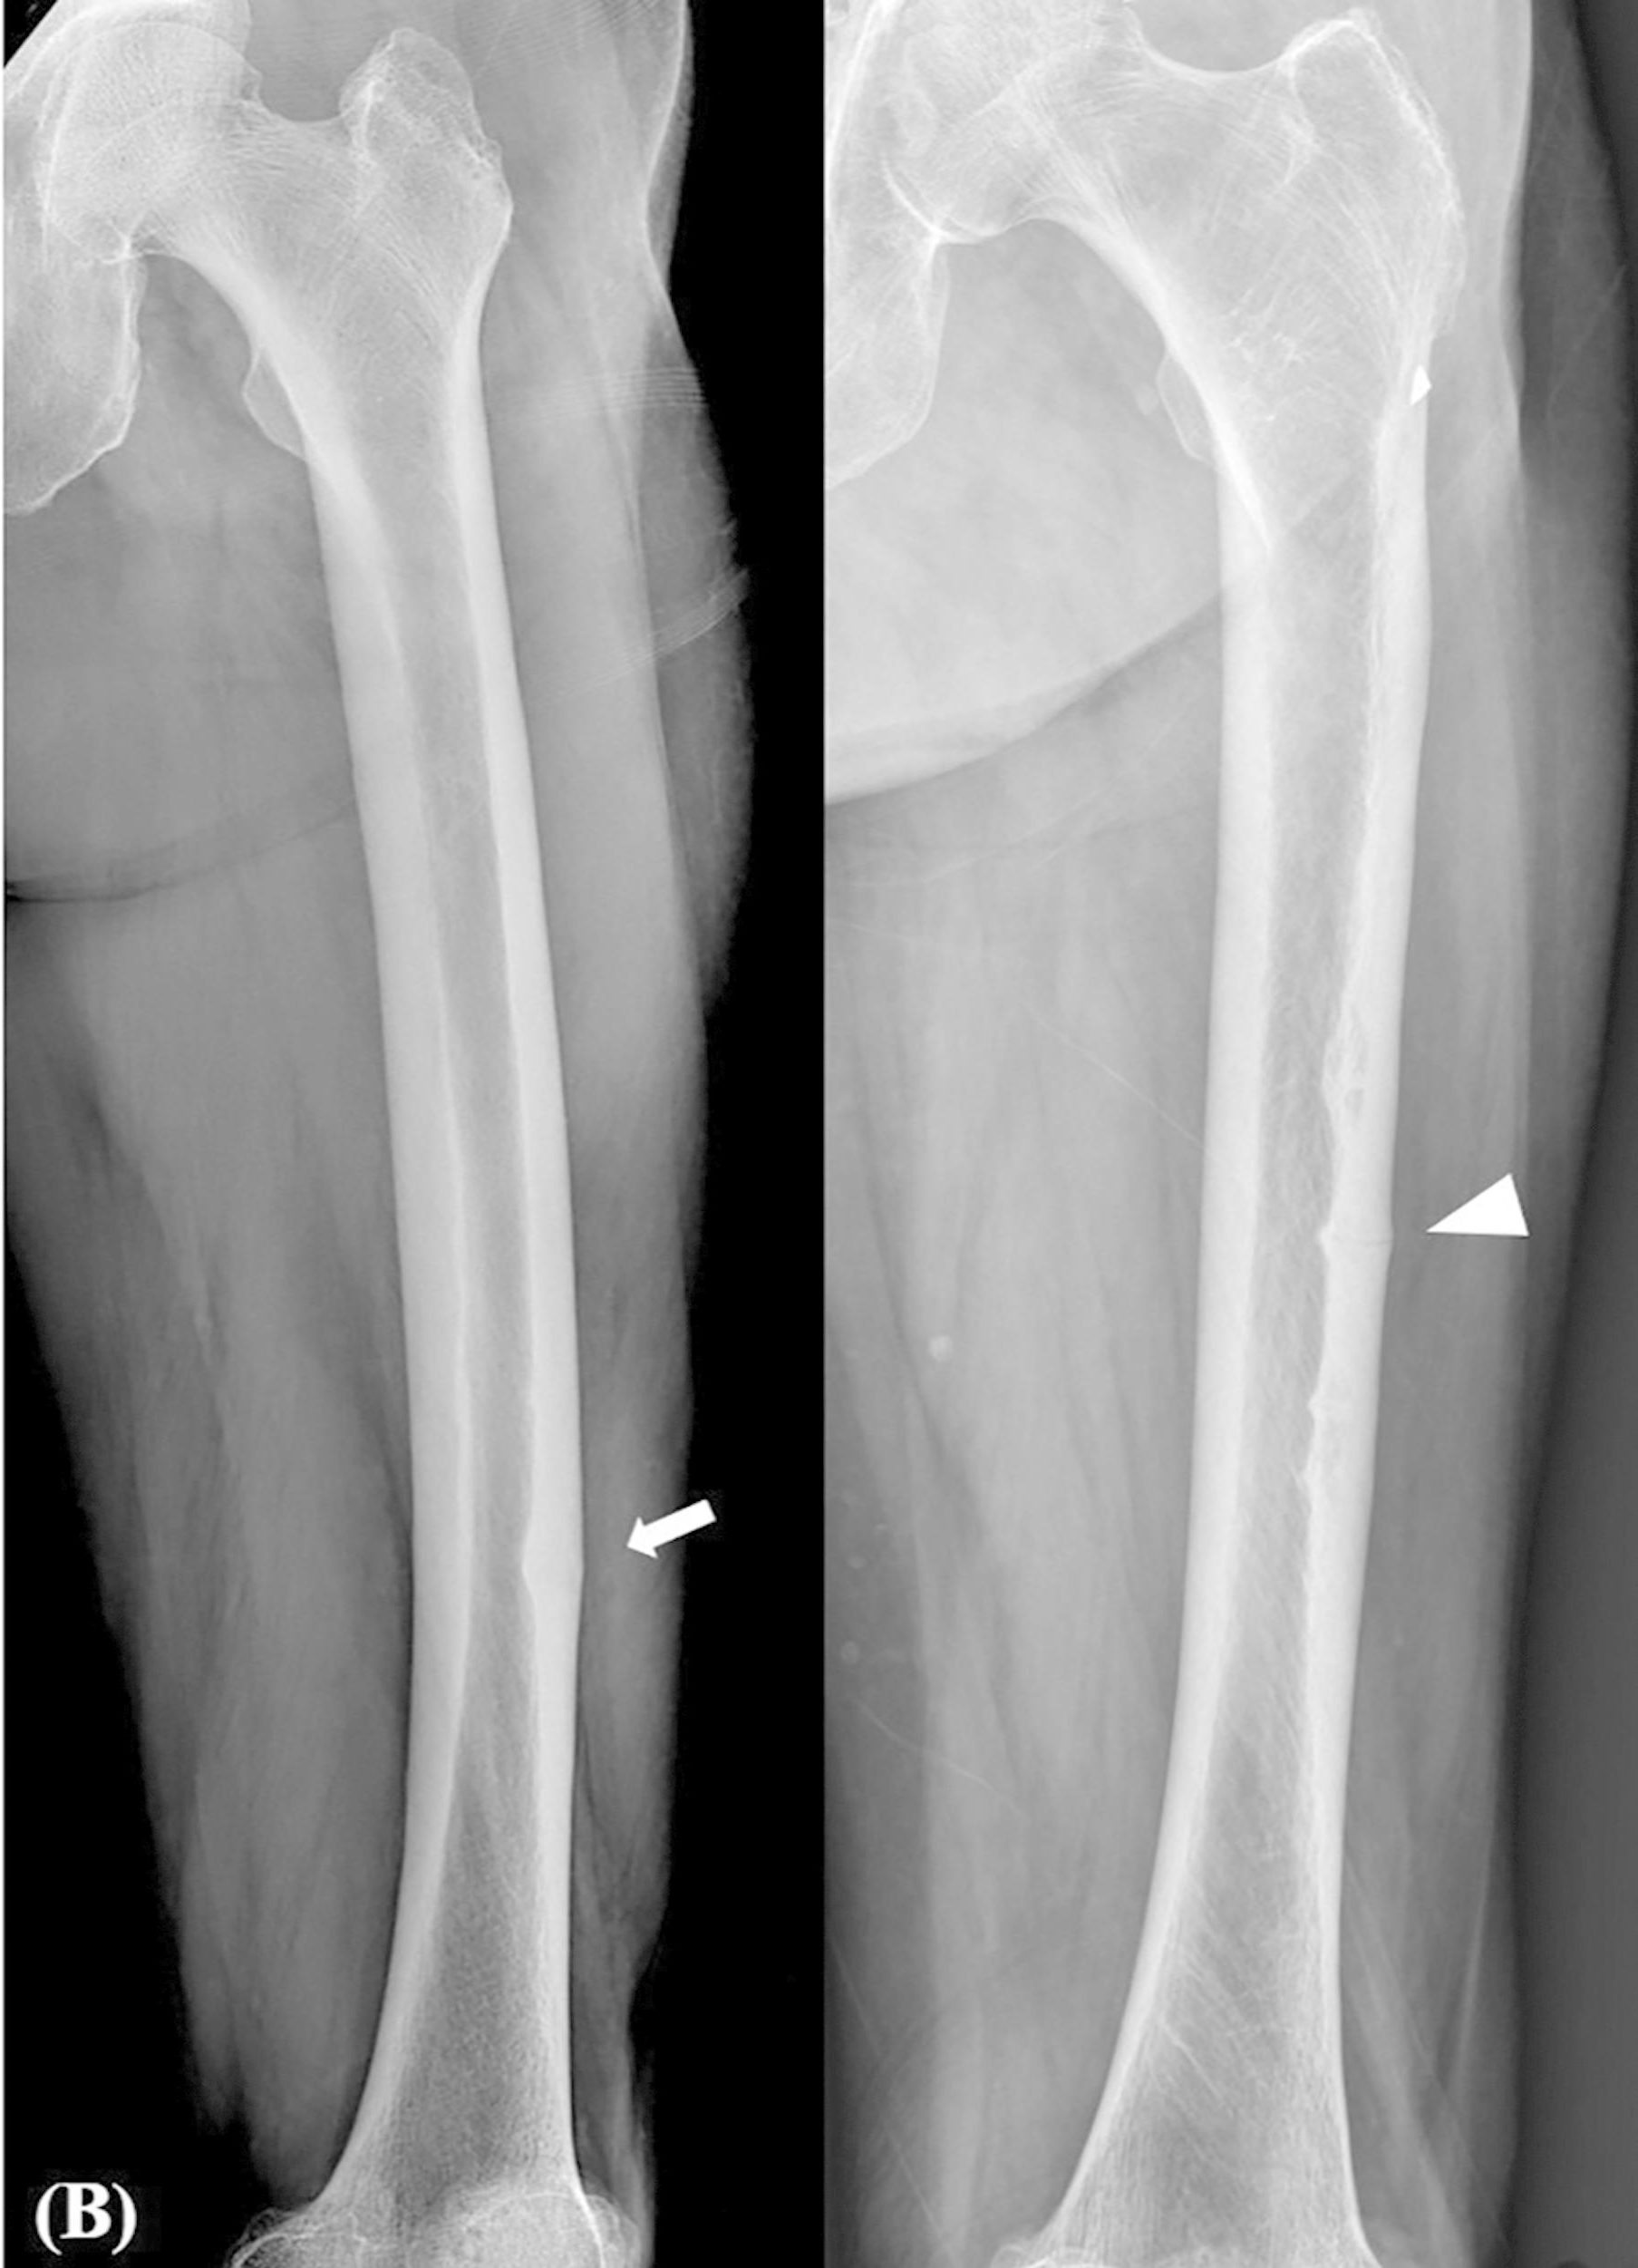

Bisphosphonates and atypical subtrochanteric fractures of the femur Bisphosphonates Prior To Orthopedic Surgery Orthopedic surgeons could consider bisphosphonates for up to 1 year postoperatively regardless of the patient’s prior bone mineral. These 2 studies together suggest bisphosphonate use prior to fracture may impede radiographic fracture healing but do not appear to. This article reviews the current use of bisphosphonates in orthopedic surgery. There are concerns that administration of bisphosphonate (bp) can. Bisphosphonate use. Bisphosphonates Prior To Orthopedic Surgery.

BisphosphonateRelated Complete Atypical Subtrochanteric Femoral Bisphosphonates Prior To Orthopedic Surgery Bisphosphonate use was associated with a higher risk of periprosthetic fractures in younger patients with normal bone quantity. This article reviews the current use of bisphosphonates in orthopedic surgery. There are concerns that administration of bisphosphonate (bp) can. Orthopedic surgeons could consider bisphosphonates for up to 1 year postoperatively regardless of the patient’s prior bone mineral. These 2 studies together. Bisphosphonates Prior To Orthopedic Surgery.

Figure 1 from Atypical femur fracture in an adolescent boy treated with Bisphosphonates Prior To Orthopedic Surgery These 2 studies together suggest bisphosphonate use prior to fracture may impede radiographic fracture healing but do not appear to. Orthopedic surgeons could consider bisphosphonates for up to 1 year postoperatively regardless of the patient’s prior bone mineral. There are concerns that administration of bisphosphonate (bp) can. This article reviews the current use of bisphosphonates in orthopedic surgery. Bisphosphonate use. Bisphosphonates Prior To Orthopedic Surgery.